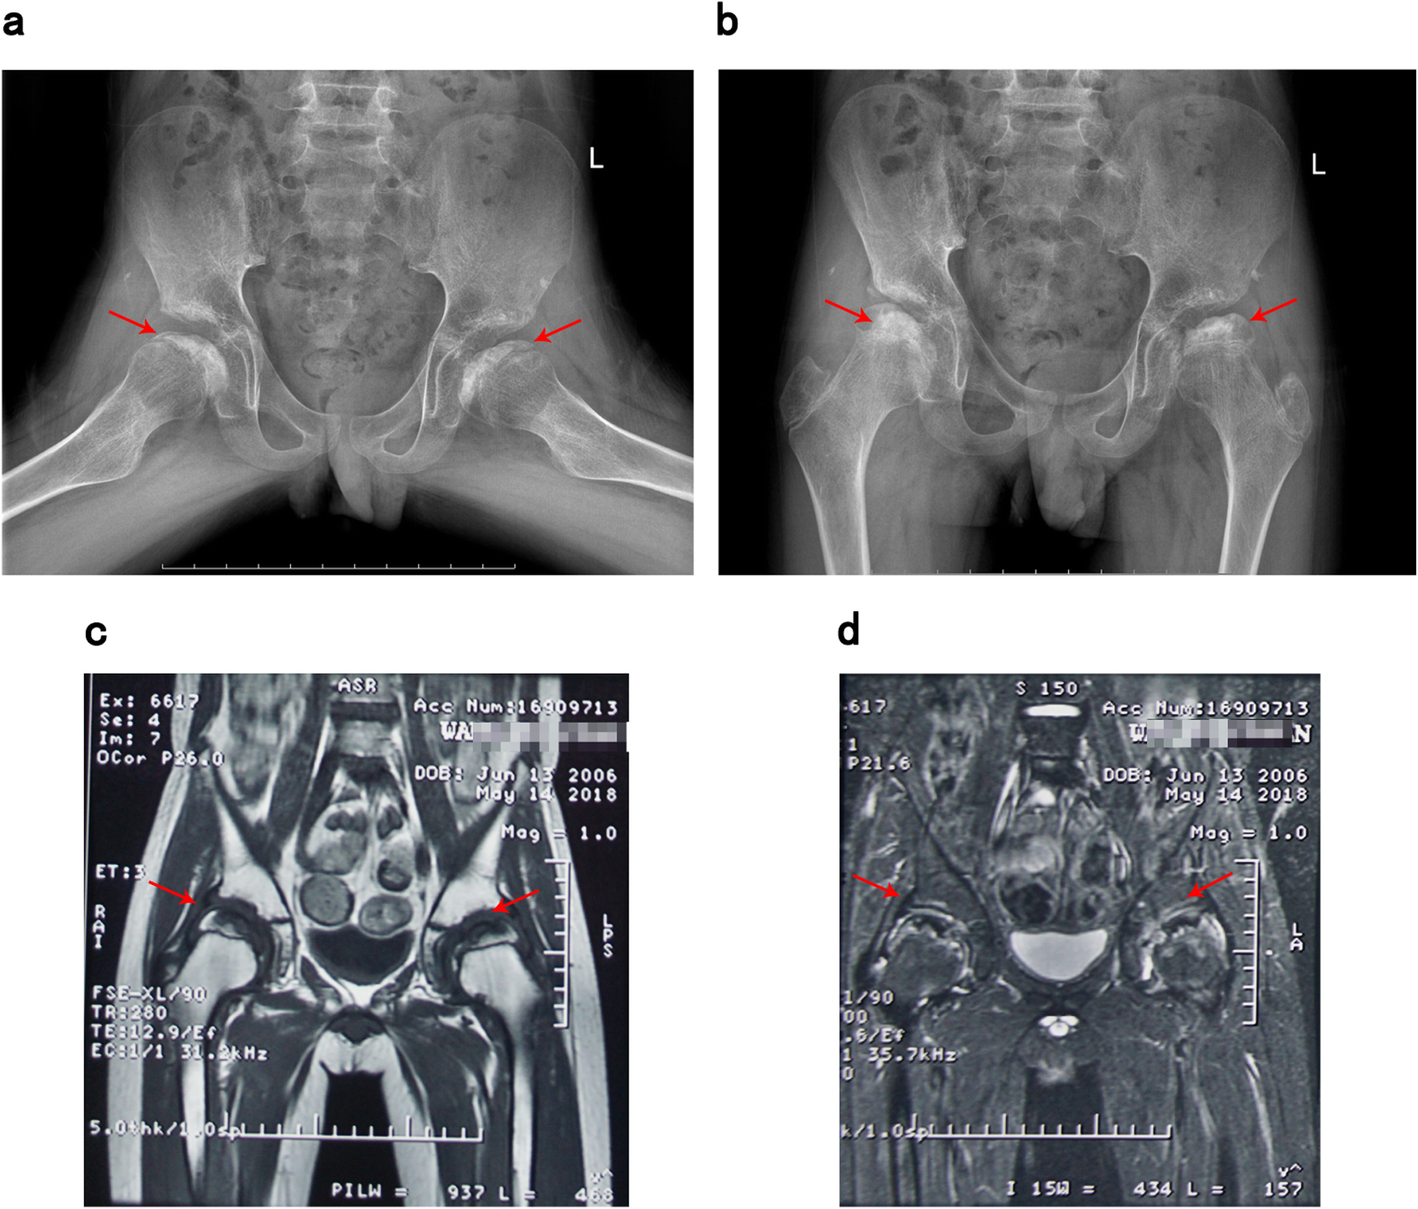

Fig. 1

Patient’s bilateral hip X-ray and magnetic resonance imaging (a-b: hip X-ray imaging; c-d: hip magnetic resonance imaging. The arrows point out pathological structures in examinations, indicating bilateral necrosis of the femoral osteoepiphysis)